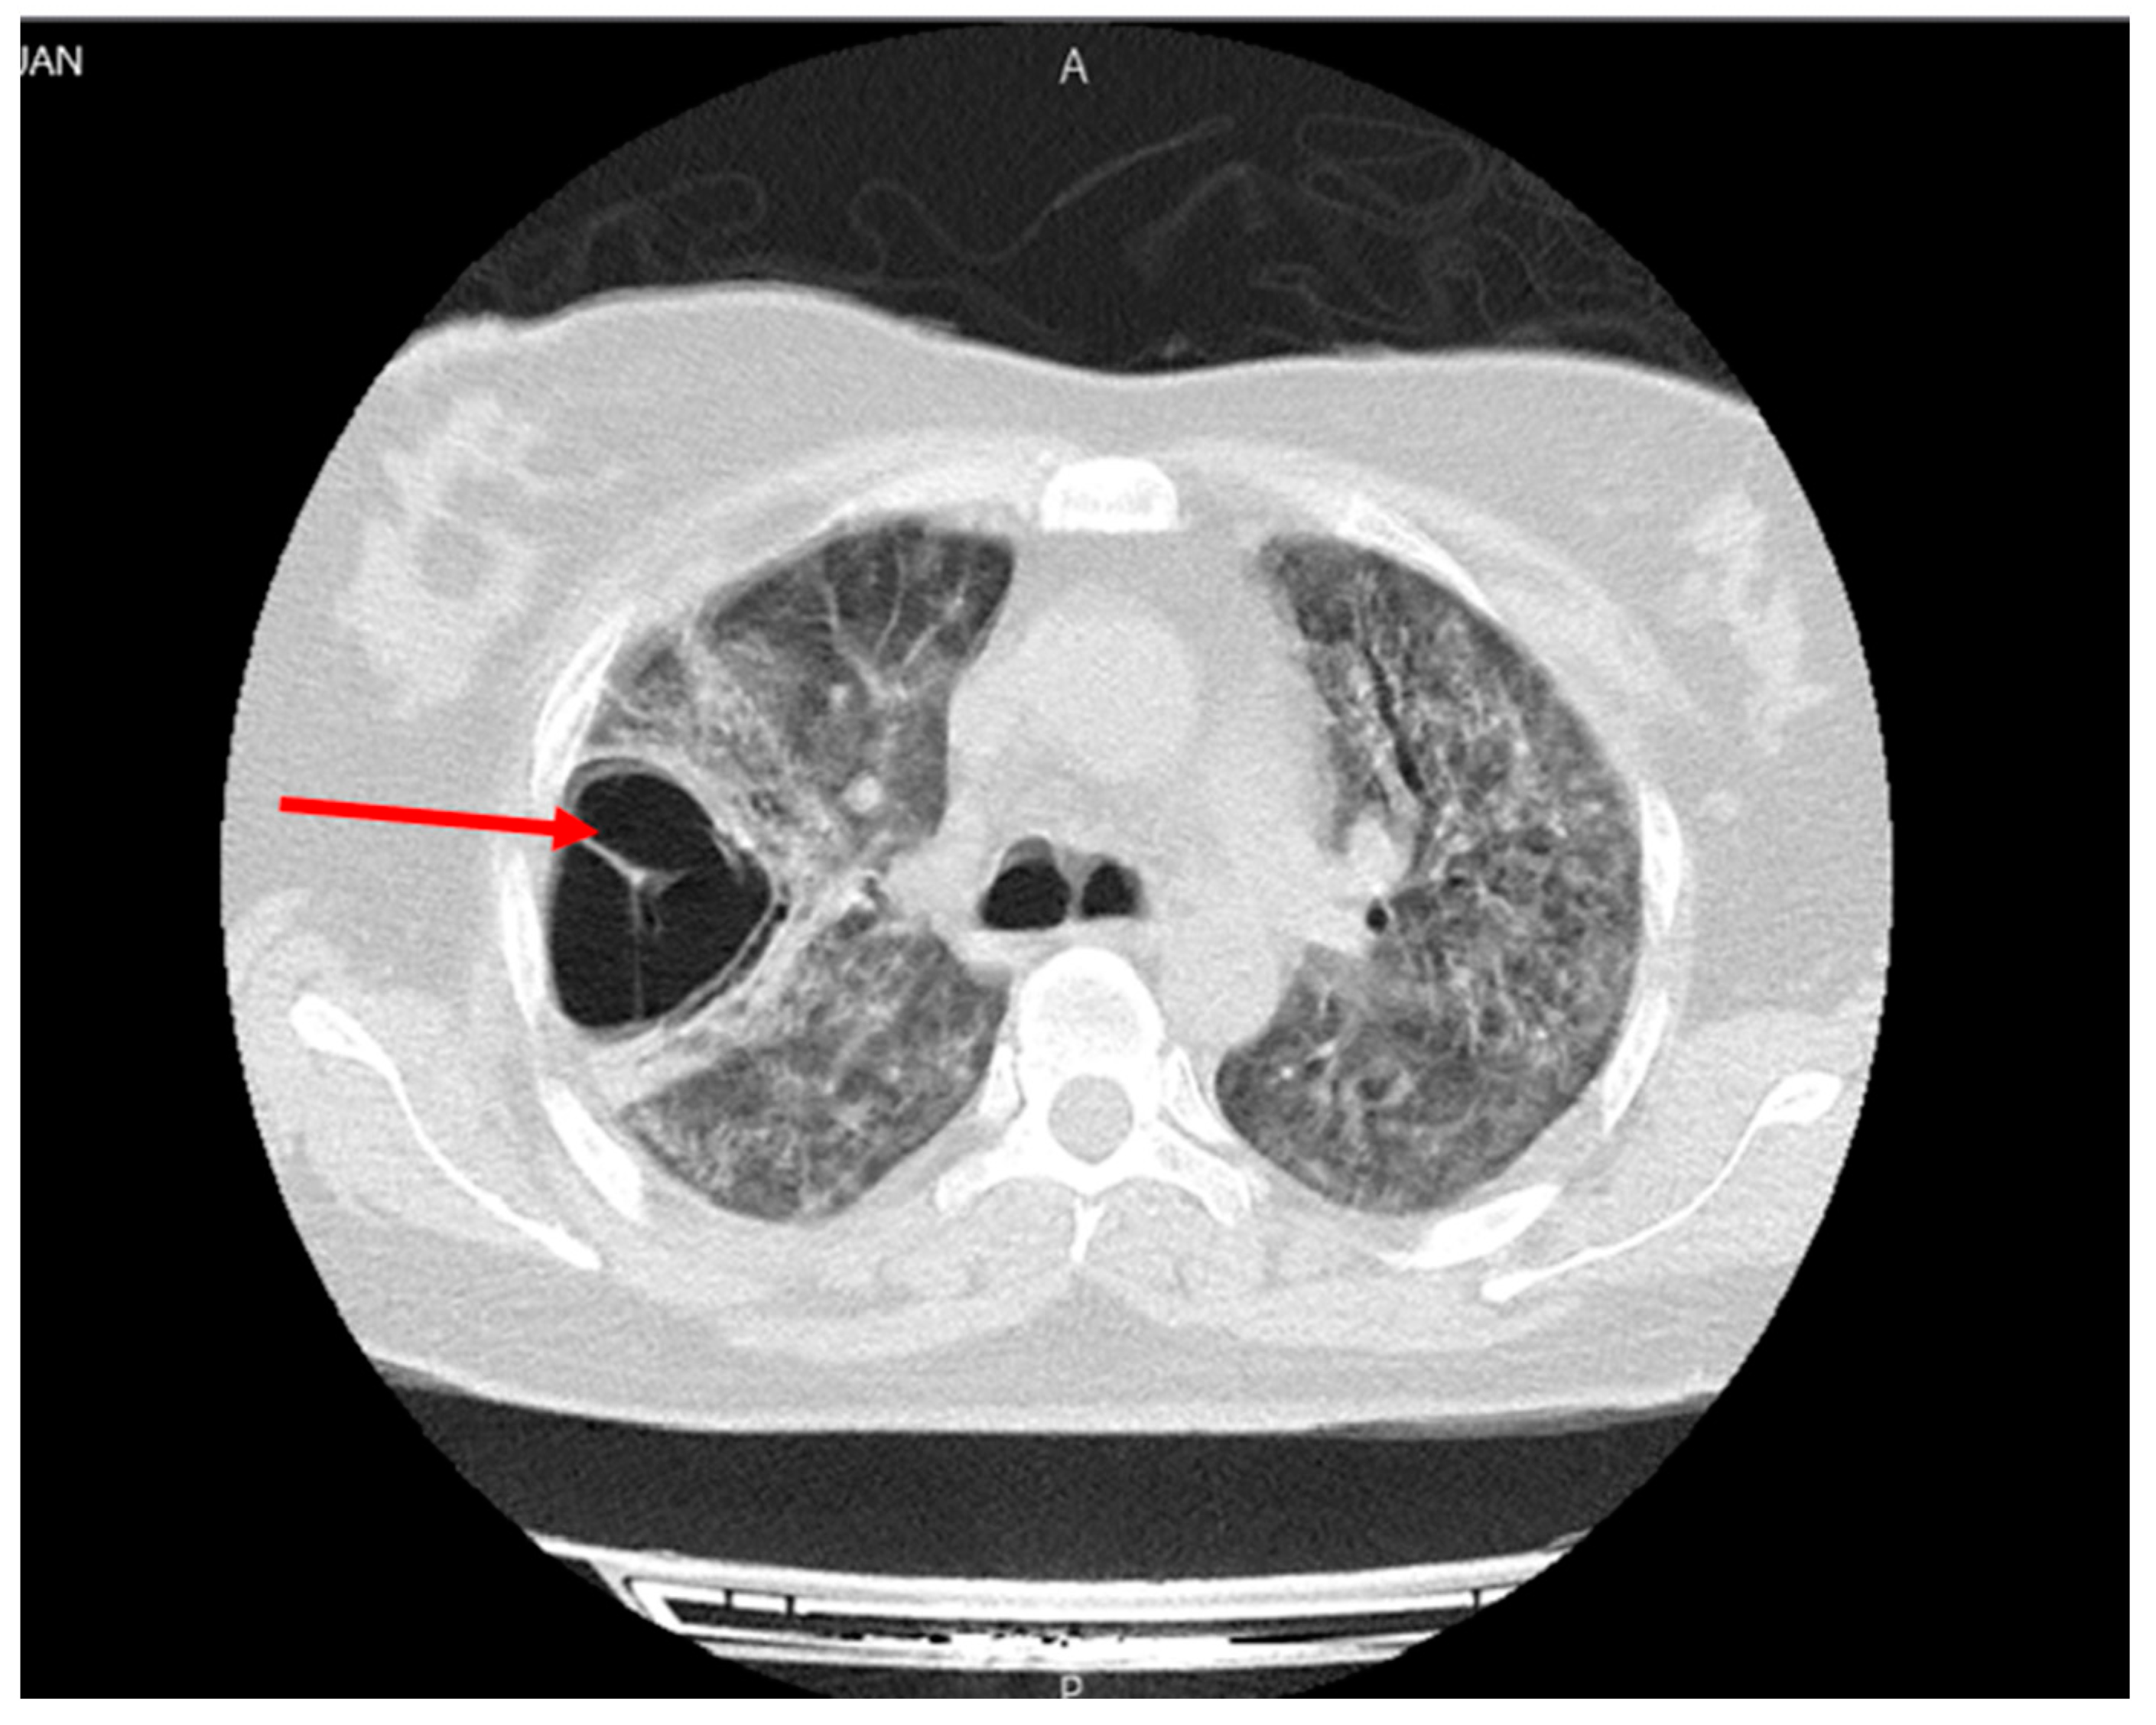

Figure 1.

Large septoid cavity in right upper lobe with the spread to the middle and lower lobes of the lung (red arrow).